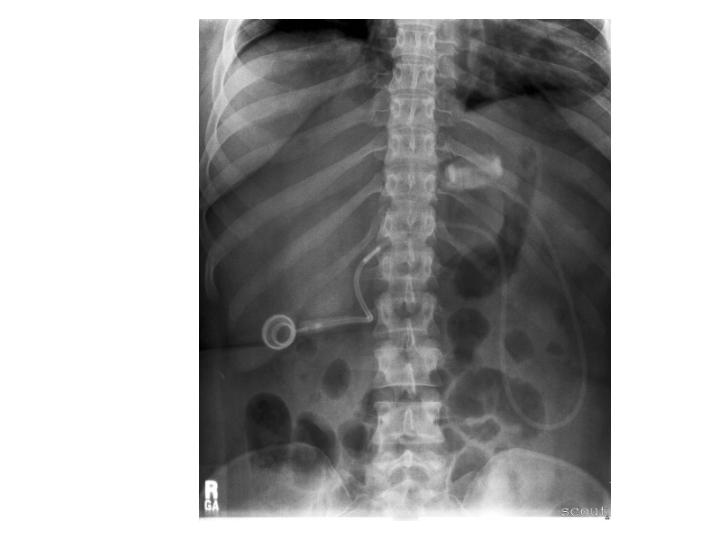

Laparoscopic gastric bypass LGBP internal hernia, plain Xray Gastric Sleeve On X Ray (left) radiograph shows an abnormal position of the gastric band , which has slipped inferiorly and rotated clockwise. Firstly, it is a restrictive procedure, meaning that it achieves weight loss by restricting. Laparoscopic sleeve gastrectomy is one of the most common bariatric procedures worldwide. The connecting tubing has also migrated into a more rightward position than expected. Sleeve gastrectomy is. Gastric Sleeve On X Ray.

Plain abdominal Xray showing an obstruction and dilated intestinal Gastric Sleeve On X Ray Firstly, it is a restrictive procedure, meaning that it achieves weight loss by restricting. The connecting tubing has also migrated into a more rightward position than expected. (left) radiograph shows an abnormal position of the gastric band , which has slipped inferiorly and rotated clockwise. The gastric sleeve works in two ways. It has recently gained in popularity. Laparoscopic sleeve. Gastric Sleeve On X Ray.